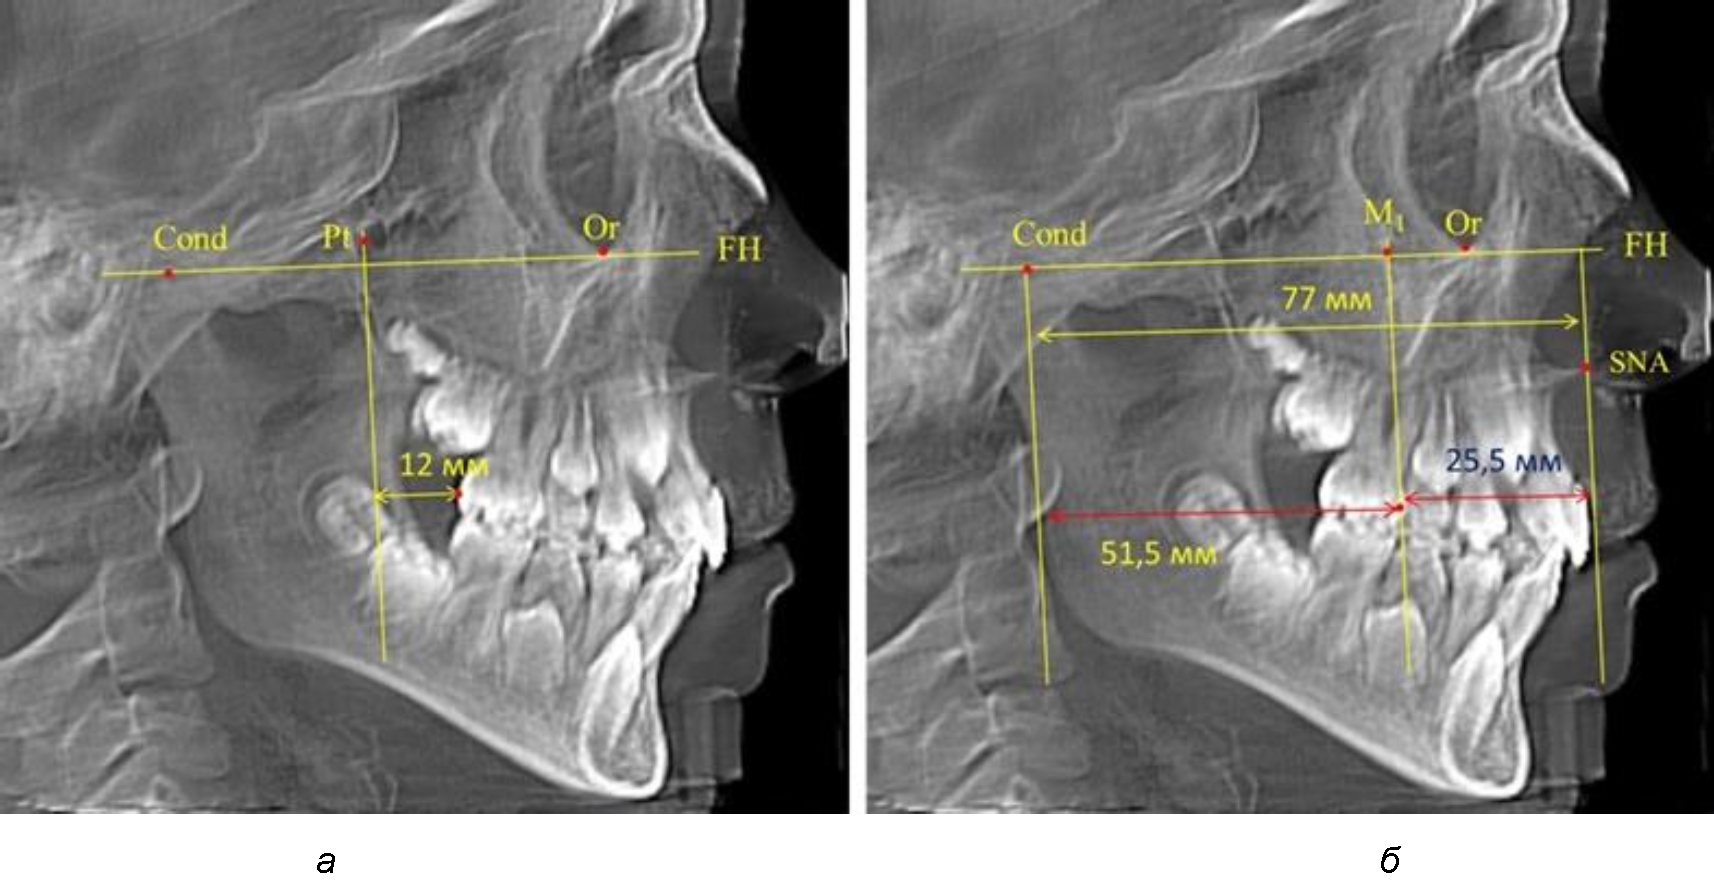

Второй частью исследования был анализ положения первых постоянных моляров в различные периоды сменного прикуса. На телерентгенограммах детей периода прикуса молочных зубов дистальная поверхность зачатка первого постоянного моляра отстояла от крыловидной вертикали на величину, составляющую около 7 мм, что было близким по значению к данным R. E. McDonald. Сагиттальный размер гантического отдела составлял около 60 мм, а его отношение к кондилярно-молярной глубине – 1,5 (рис. 4).

Рис. 4. Особенности положения первых моляров по R. E. McDonald (а) и по предложенному методу (б) у ребенка 4 лет